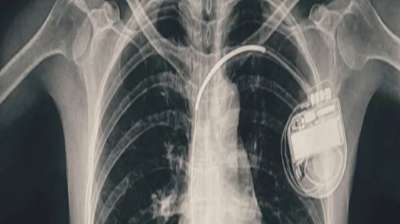

भोपाल के डॉक्टरों ने दिखाई मिसाल, हार्ट प्रॉब्लम वाली बच्ची को दी नई जिंदगी

14 Aug, 2025 05:05 PM IST | STORYLIVE.IN

भोपाल। भोपाल मेमोरियल अस्पताल एवं अनुसंधान केंद्र (बीएमएचआरसी) के कार्डियोलॉजी विभाग ने एक दुर्लभ और चुनौतीपूर्ण चिकित्सा उपलब्धि हासिल की है। यहां 13 वर्ष की गैस पीड़ित आश्रित बालिका को...